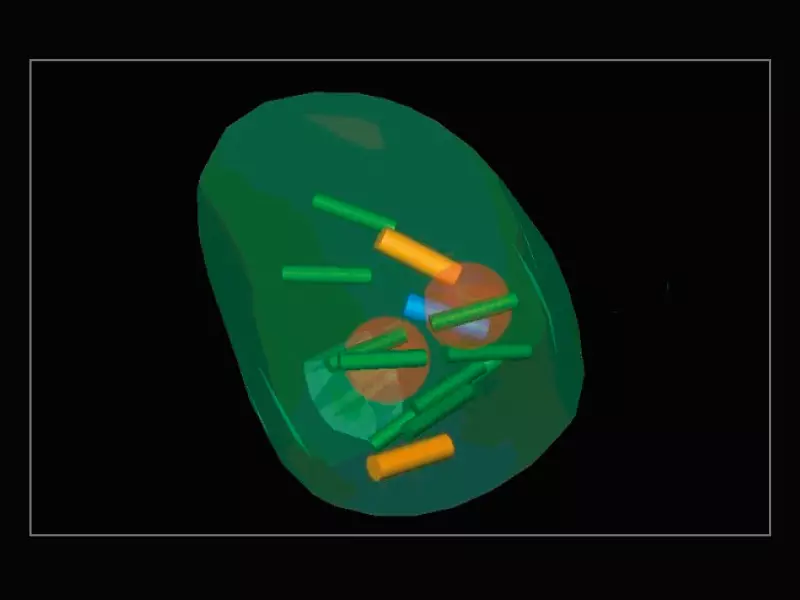

MyLab™E80 - Urofusion - Systematic Biopsy Guide

MyLab™E80 - Urofusion - Systematic Biopsy Guide

MyLab™E80 - Urofusion - Sample Mapping

MyLab™E80 - Urofusion - Sample Mapping